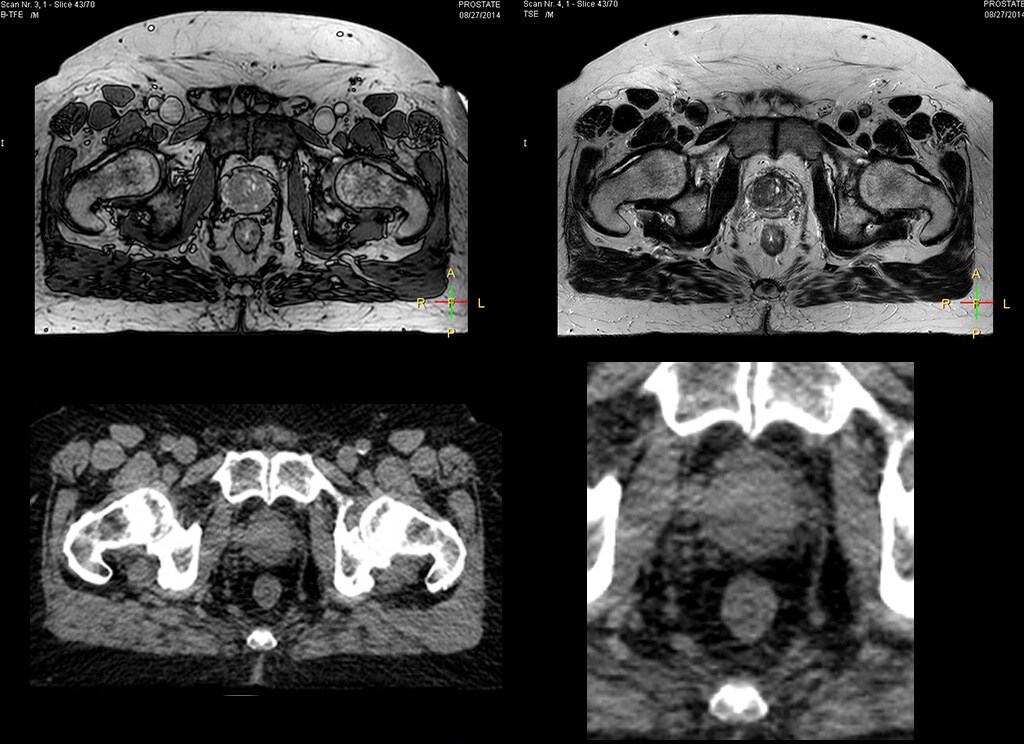

“The biggest problem for CT-based planning, especially in prostate, is you can’t see the cancer very well,” says Dr. Stevens. “On CT it can be quite challenging to see the edge of the prostate especially at the apex. When the edge of the prostate can’t be delineated well on CT, radiation oncologists will increase their margins a little bit so they don’t miss it, but that can also increase toxicity.” “Using MR, the prostate is well delineated. We quickly see the edges of cancerous tumors like in prostate cancer, and as normal structures can be defined, we can optimize the treatment plan to protect these organs and their normal function. This can potentially improve the outcome. And it improves workflow as well. We can contour more quickly, confident that the tumor is going to be in the field.” “The Ingenia 3.0T MR scanner provides high resolution allowing us to make scans fast for the patients. It also gives the potential to include methods like MR spectroscopy and diffusion weighted Imaging, which we’re in the process of doing right now,” Dr. Stevens adds.

Beaumont Health System (Royal Oak, Michigan, USA) is one of the largest health systems in the USA, with eight hospitals and 153 outpatient sites, a medical school and a research institute. The Radiation Oncology (RO) department houses a dedicated Ingenia MR-RT solution that is routinely used for clinical and research MR-RT activities. “The main reason to integrate MR imaging in RT planning is the superb soft tissue contrast that allows detailed delineation of tumors and healthy organs, which is crucial for RT planning,” says Craig W. Stevens MD, PhD. “MR also provides information on functional and biological activities in tumors, background tissue and normal organs, which may also be used in RT planning,” says physicist Di Yan, DSc, FAAPM.” “We currently use MR-RT mainly in the abdomen and pelvis region: prostate, colorectal, pancreatic, cervical, and liver. Also in the brain, we are starting to use it,” says Dr. Yan.